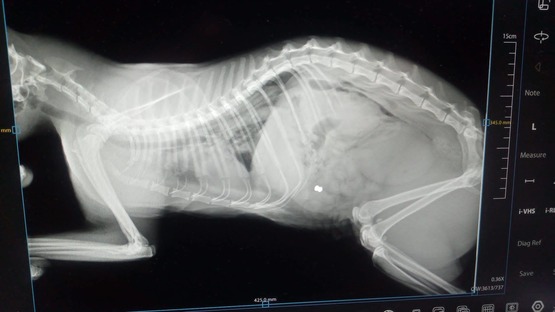

Rentgena izmeklēšanas laikā ārsti kaķa ķermenī atklāja iestrēgušu lodi. Tiek pieļauts, ka ievainojums gūts agrāk. Notikušā apstākļi nav zināmi. Patversmē uzsver, ka, neskatoties uz piedzīvoto, Koļa joprojām uzticas cilvēkiem, ir mīļš un labprāt pieņem aprūpi.